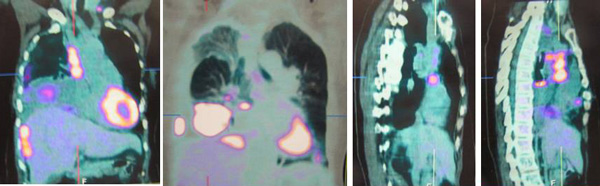

SH said she was well all these years and her progress was monitored by her doctor. About 10 years later, in early 2009, SH developed shortness of breath. She could not lift her left arm. She was tired and lost her appetite. A chest X-ray indicated large left pleural effusion. SH had the fluid in her lung tapped out. A CT scan on 7 January 2009 indicated several subcentimeter nodules in her left lung. The lymph nodes in the left axilla and aortopulmonary window were enlarged. Impression: left pulmonary and pleural metastasis.

SH sought a second opinion from another oncologist at a university hospital. Another CT scan was performed and it also confirmed a metastatic breast cancer with left pleural effusion with small benign liver cysts.

A bone scan done on 29 January 2009 indicated multiple skeletal metastases in the sternum and two ribs on the left side.

In August 2011 SH developed shortness of breath again. A CT scan on 4 August 2011 confirmed presence of mild left pleural effusion. Fluid was tapped out of her lung again.

A bone scan done on 18 March 2011 indicated “sclerotic bone metastases in manubrium showing activity.” SH was told that if Aromasin did not work for her, she would have to undergo intravenous chemotherapy.